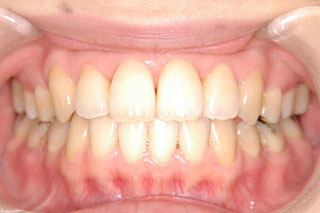

2年半ほどの治療で、装置を撤去し保定治療に移行しています。概ね緊密な臼歯の咬合と前歯の被蓋が確立されました。

保定治療を開始してから2年半が経過していますが、良好な咬合の安定が維持されています。見た目だけではなく、中心位マウントの咬合器にて顎位のズレを計測していますが、計測値は1mm未満の数値である事を確認しています。理想的には中心位=咬合位かも知れませんが、多少の遊びは必ず出てきます。しかしながら最初からルーズなゴールを目指していたら、的を外してしまうでしょう。できれば、ピンポイントで理想を目指したいものです。